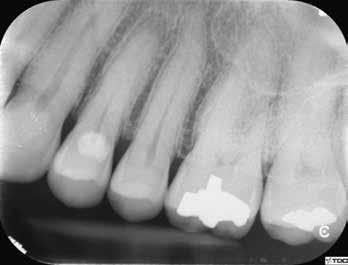

1. a–g. ábrák: A direkt pulpasapkázás lépései. Kiindulási bitewing-felvétel: A meglévő restaurátum közel helyezkedett el a pulpakamrához (a). Kiindulási periapicalis felvétel: Nincs periapicalis elváltozás fennállására utaló jel (b). A pulpaexpozíció (c). A vérzéscsillapítás céljából 20 másodpercen keresztül steril vattagombóccal történő kompressziót követően látható pulpaseb (d). A pulpasapkázás céljából behelyezett anyag, a széli részek tisztázása előtt készült felvétel (e). A röntgenárnyékot nem adó ideiglenes tömés behelyezése után készült felvétel (f). Az első ülés végén a röntgenárnyékot nem adó ideiglenes töméssel ellátott fogról készített röntgenfelvétel (g).

2. ábra: A hat hónapos kontroll alkalmával készített röntgenfelvételen vastag dentinhíd látható a pulpasapkázó anyag alatt.

3. ábra: A hároméves kontroll alkalmával készített röntgenfelvételen megfigyelhető a restaurátum pontos illeszkedése.

A kezelést követően a beteg tünetmentes volt. A kérdéses fog a kontrollvizsgálatok során végzett szenzibilitástesztekre fiziológiás reakciókat adott. A hat hónapos kontroll alkalmával készített röntgenfelvételen a sérülésnek megfelelően széles dentinhidat észleltünk (2. ábra). A restaurátum a hároméves kontroll során is megfelelőnek bizonyult (3. ábra)